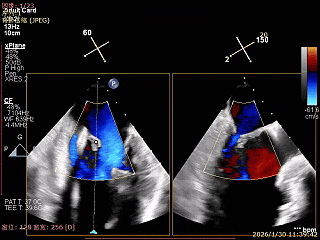

夹子内侧反流消失

夹子外侧残余脱垂与反流

3D Enface下组织桥稳定残余外侧前叶脱垂

3D Enface上彩可见夹子内侧无反流,残余外侧反流

3D Enface下组织桥稳定无反流

夹子释放后,反流基本消失

LVOT切面可见主瓣二尖瓣术后反流基本消失